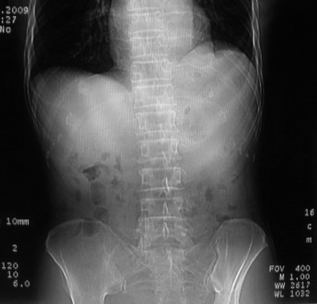

男,66岁,贲门ca术后一年,喝了5、6杯水了。怎么描述跟诊断啊